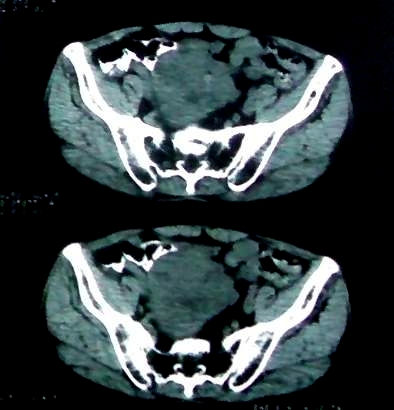

男 60岁,下腹部肿块半年余

不排除间质瘤并腹膜后转移可能。

腹膜后肿瘤。间叶瘤。

病理结果:肠系膜肉瘤

肠系膜的原发性肠系膜肿瘤比较少见,大体可分为囊性和实性两类。囊性肿瘤多为良性。实性肿瘤可以为良性和恶性,恶性肿瘤以恶性淋巴瘤为最多,其次是脂肪肉瘤、平滑肌肉瘤、纤维肉瘤等。恶性肿瘤约占实体肿瘤的6% [1] 。文献资料显示原发性肠系膜肿瘤约7%位于小肠系膜,其中60%位于回肠系膜和肠系膜根部,结肠系膜和阑尾系膜仅占20%左右 [2] 。由于肠系膜肿瘤在临床上不多见,症状无特异性,起病隐匿,早期可无症状,只有当肿瘤增大压迫周围的组织脏器时,才有可能出现相应的症状,并且这些症状常与邻近器官受压有关。腹部包块是主要的症状,临床表现为发热、乏力、腹部隐痛不适和饱胀感、消瘦,偶有呕吐及便秘,当肿瘤出血和囊肿突然增大时,可有腹痛,压迫症状有肠梗阻,下肢肿胀,肾盂积水等表现。体格检查时可触及腹部肿块,且活动度好,尤其是横向移动。b超可早期发现腹块,并可确定大小、性质及部位。x线钡剂灌肠检查,虽然不能提供系膜肿瘤的直接诊断依据,可显示为与肠管关系密切之外在性肿物,并可排除肠管、泌尿系等疾病[3] 。腹腔镜对原因不明的腹痛及性质不明的腹块,既可定性又可定位,其正确诊断率为74% [4] 。肠系膜良性肿瘤和恶性肿瘤的病程长短进行比较,恶性肿瘤绝大多数病程均在半年以内,没有超过2年以上。良性肿瘤大多数病程均在2年以上。这一点在诊断上具有鉴别意义。

病灶形态不规则,偏心性裂隙样坏死,支持恶性病变。来源不好定。感谢反馈结果--肠系膜肉瘤。